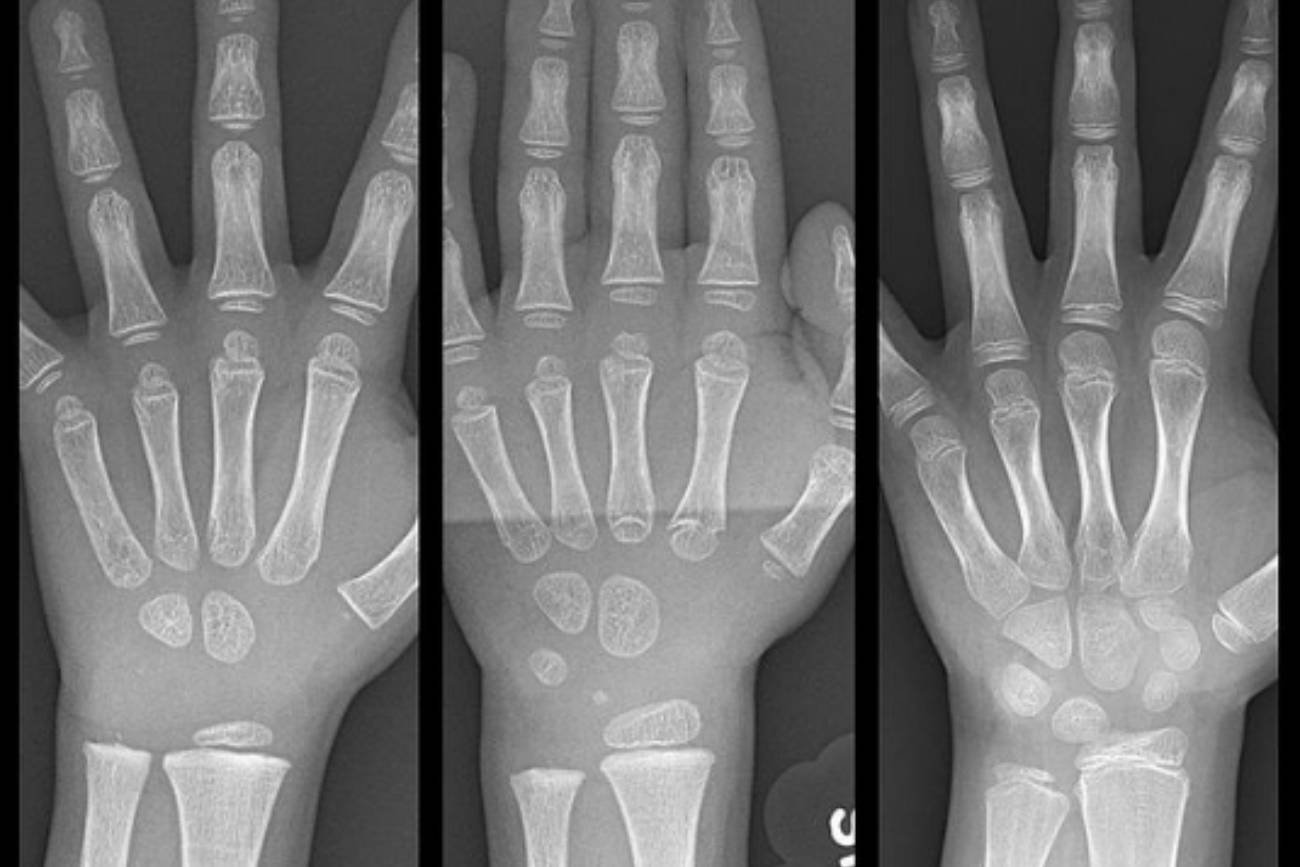

Niesamowite zdjęcia rozwoju dłoni dziecka

Na zdjęciach pokazanych na Instagramie, obie specjalistki zwracają uwagę na to, że możemy tam zobaczyć, jak zmienia się rozwój kości w dłoniach malucha w wieku 3, 4 i 8 lat. Im mniej rozwinięta ręka, tym kostnienie chrząstek jest mniejsze. Proces ten u dziecka powinien następować latami, a nie tak, jak jest to widoczne na zdjęciu w ciągu kilku krótkich lat, gdy dziecko już od 3. roku życia trzymało w ręku długopis i pisało znaczki w zeszycie.Dzieci przed 4.-5. rokiem życia nie są zdolne do poprawnego trzymania ołówka czy długopisu, nie mają siły w ciele, by odpowiednio naciskać narzędzia piśmiennicze. I przede wszystkim – w tym wieku należy postawić na jego rozwój motoryki dużej, czyli całego ciała, a nie skupiać się na palcach i dłoniach (czyli motoryce małej).